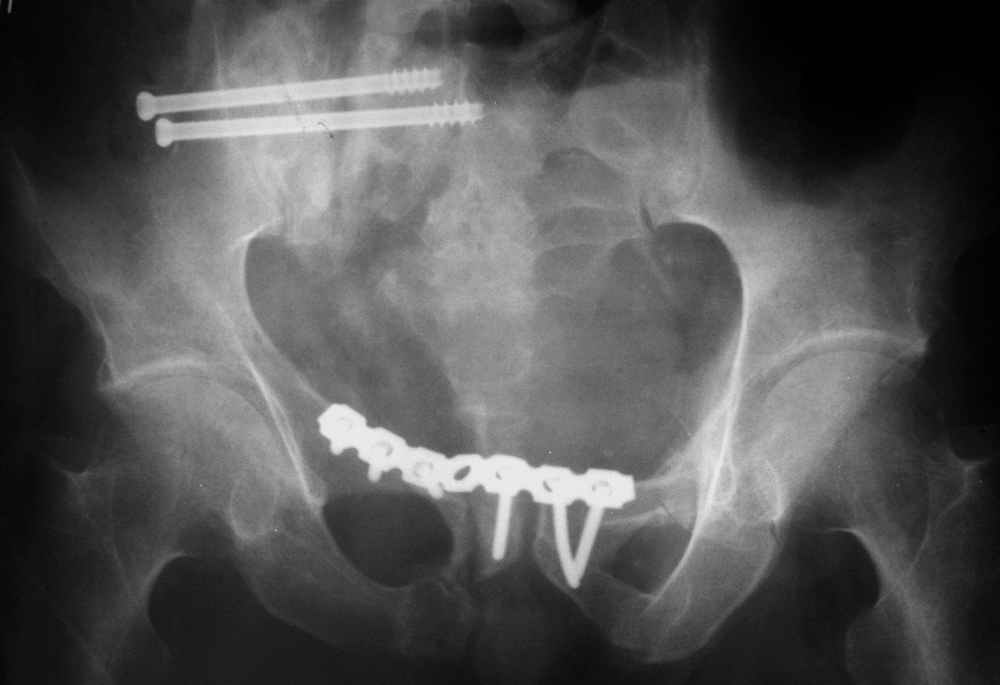

отеотомия передних и задних отделов, дистракция аппаратом

окончательная фиксация